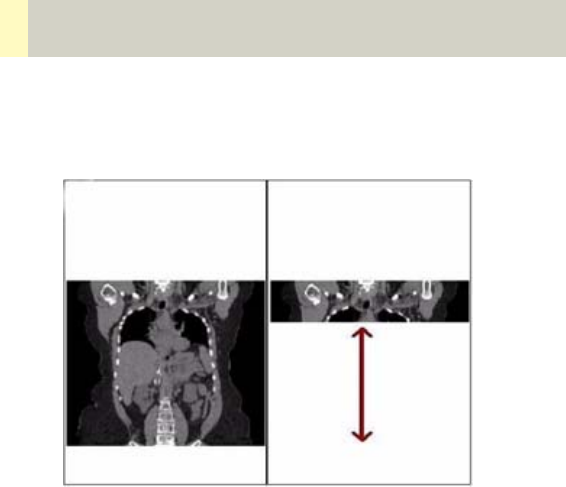

•Radiation Therapy Planning 462

•Workflow 468

•Scan Protocols 470

- Overview 470

- RT_Head 472

- RT_Thorax 474

- RT_Breast 476

- RT_Abdomen 478

- RT_Pelvis 480

- Additional Important Information 482